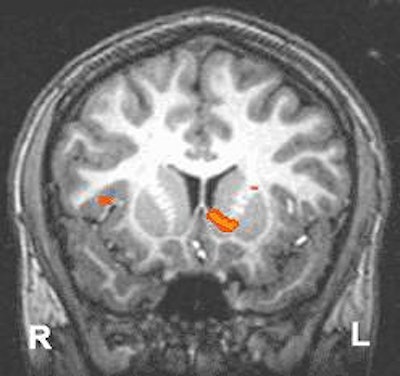

Functional MRI detects regions in the brain where extra oxygen in the blood flows in response to events in the environment. The scans depict the ventral striatum, known to be involved in motivating organisms to seek natural (such as food and sex) and artificial (such as street drugs) rewards. In young adults (above), both sides of the ventral striatum were robustly activated by the prospect of responding to win a reward. In adolescents (below), the ventral striatum showed less activation. Images and caption courtesy of NIAAA’s Laboratory of Clinical Studies Section of Brain Electrophysiology and Imaging.

According to the results, the adolescents and the young adults performed similarly on the MID task, with an overall hit rate of 69.9%. Both groups reported greater happiness at winning and greater fearfulness at losing based on the answers to a questionnaire. With regard to anticipation of gain, both showed bilateral activation of the nucleus accumbens (NAcc). Gain versus non-gain outcomes also stimulated several portions of the prefrontal cortex and the putamen bilaterally.

However, the results indicated reduced gain anticipation activation in the right ventral striatum (VS) of the adolescents, centered in the NAcc. This right-selective deficit in recruitment of the VS may reflect developmental deficits in attention control in the adolescents during the MID task, the authors reported. In comparison, the adults demonstrated orderly activation in the right NAcc, especially as the dollar amounts increased.

"This finding provides support for an adolescent VS activation deficient (in) adolescent risky behavior, in which adolescents may seek more extreme incentives as a way of compensating for low VS activity levels," they wrote. "These data are also consistent with findings from psychosocial research that adolescents are less optimistically biased about obtaining future rewards compared with adults."